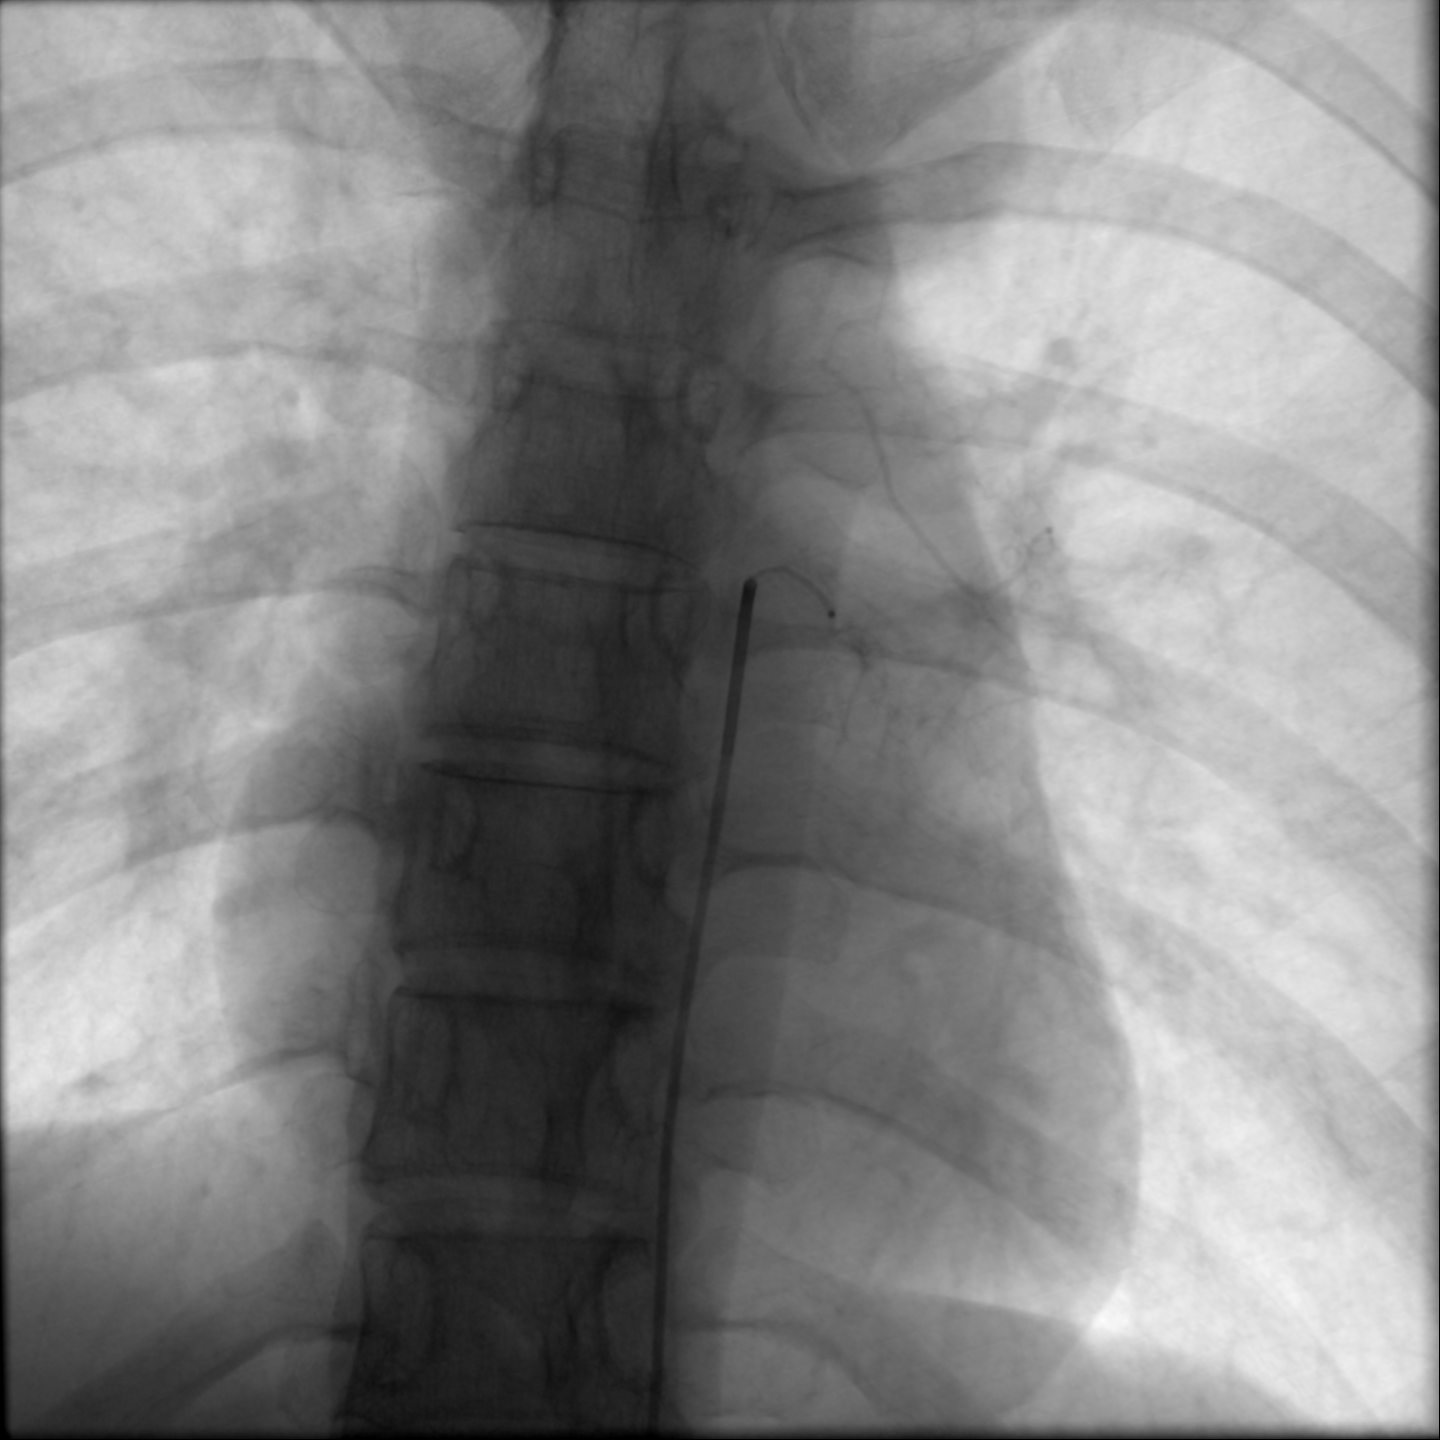

第一步是动脉造影。医生经股动脉穿刺,将一根纤细的导管送至胸主动脉,注入造影剂。瞬间,清晰的血管影像实时呈现在数字减影血管造影(DSA)屏幕上。可以明显看到,肿瘤区域有数根异常增粗、迂曲的血管(主要为肋间动脉)正如同“河流”般源源不断地向肿瘤组织输送血液。

接下来是手术最精妙的环节:超选择性血管栓塞术。满新贺操控着更细微的微导管,如同驾驶飞船在复杂的血管迷宫中穿梭。他们凭借精湛的技艺和丰富的经验,小心翼翼地避开供应正常脊髓和重要器官的血管分支,将微导管头端精准地置于每一根为肿瘤供血的靶血管内。

“位置完美,可以栓塞!”确认无误后,一种特制的栓塞微粒被缓缓注入,这些微粒随着血流精准地沉积在肿瘤的血管巢中,形成栓塞,彻底阻断了血流。屏幕上,原本显示肿瘤血供的浓密“染色”区域逐渐变淡、消失。

手术历时一个多小时,全程患者清醒,仅在大腿根部留下一个微小穿刺点。术后造影证实,肿瘤的主要供血动脉已被成功“封闭”。